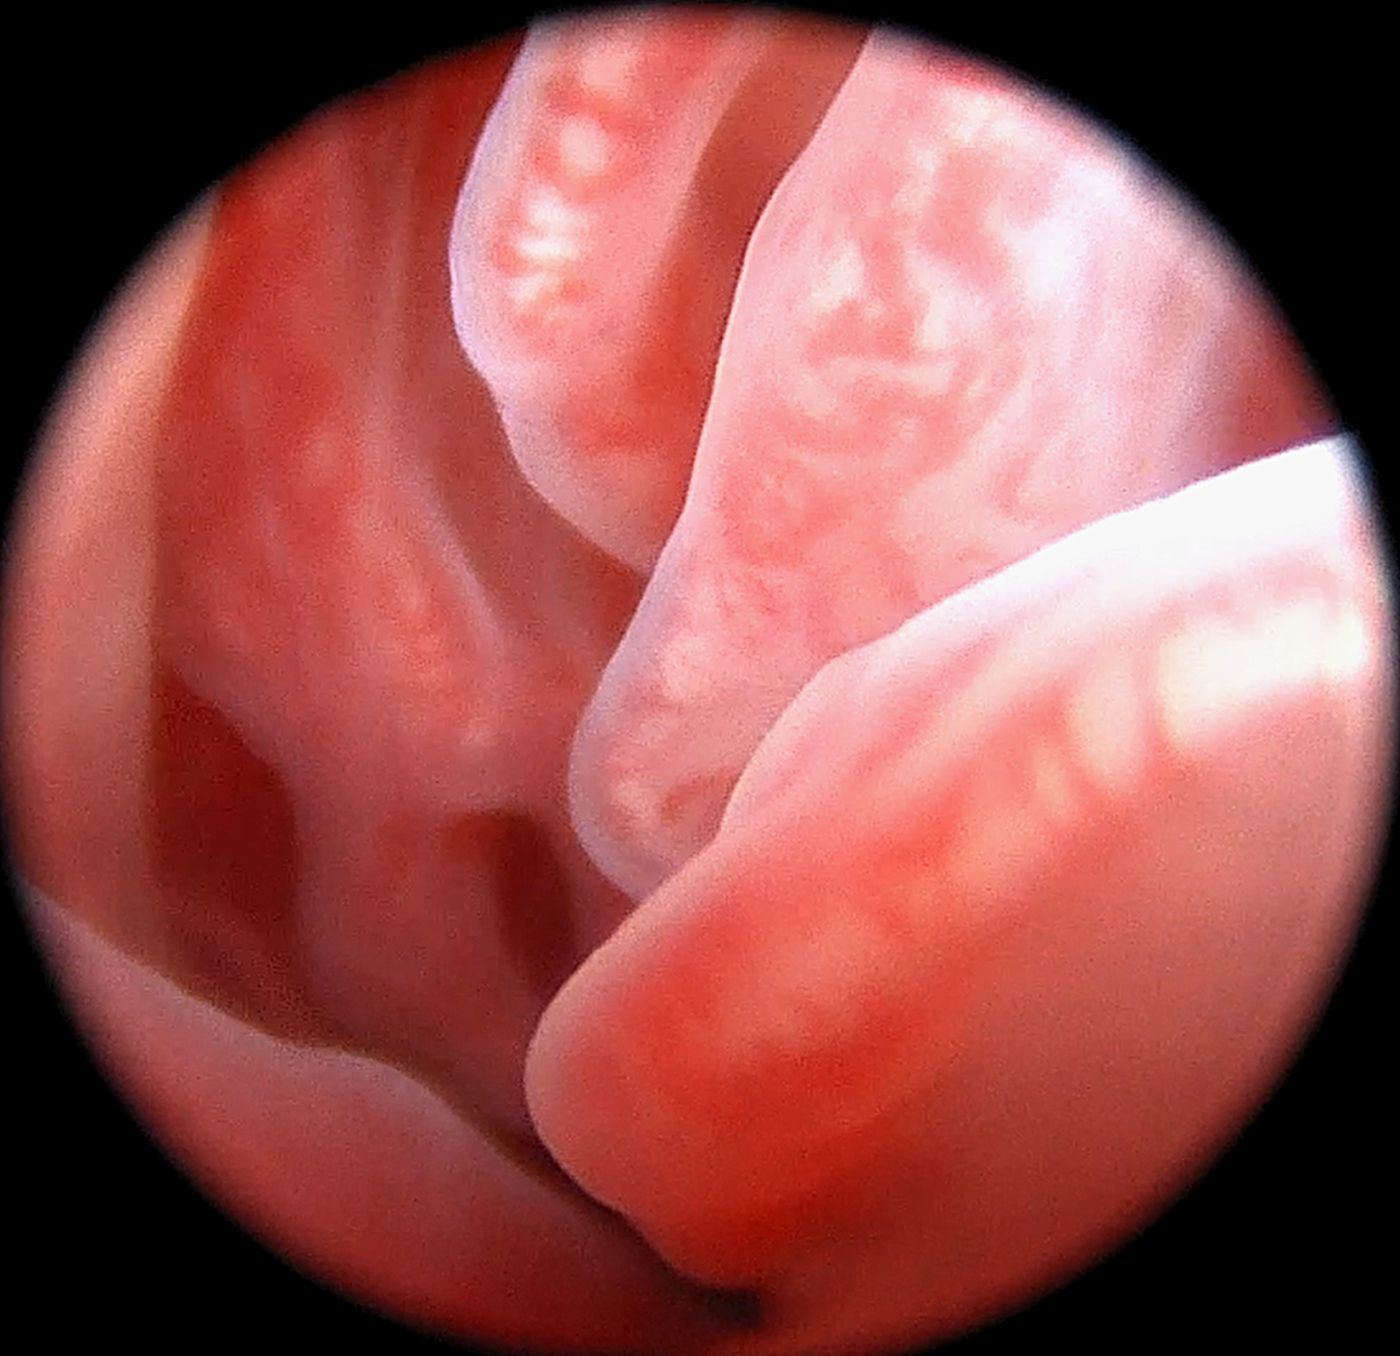

Diagnostyka endoskopowa jamy nosowej (rinoskopia przednia, rinoskopia tylna)

Zalecana w przypadku:

Przewlekły (ropny, śluzowy) wypływ z nosa

Krwotok lub kropelkowanie krwi z nosa

Trudności z oddychaniem

Asymetria jam nosowych, obrzęk okolicy nosa

Podejrzenie zmian rozrostowych

Ciała obce

Wykonujemy:

Diagnostykę z pobraniem próbek do badań mikrobiologicznych oraz histopatologicznych

Resekcję zmian nowotworowych w obrębie jam nosowych

Leczenie stenozy nosogardzieli

Usuwanie polipów zapalnych

Leczenie grzybicy jam nosowych